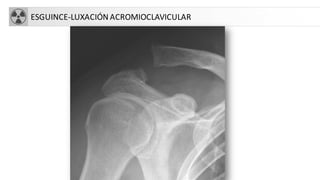

ESGUINCE-LUXACIÓN ACROMIOCLAVICULAR

• Traumatismos directos al caer sobre el hombro o

indirectos por apoyo de mano con brazo en extensión

• Se establecen hasta 6 grados, valorando:

– Ligamento acromioclavicular

– Articulación acromioclavicular

– Ligamentos coracoclaviculares